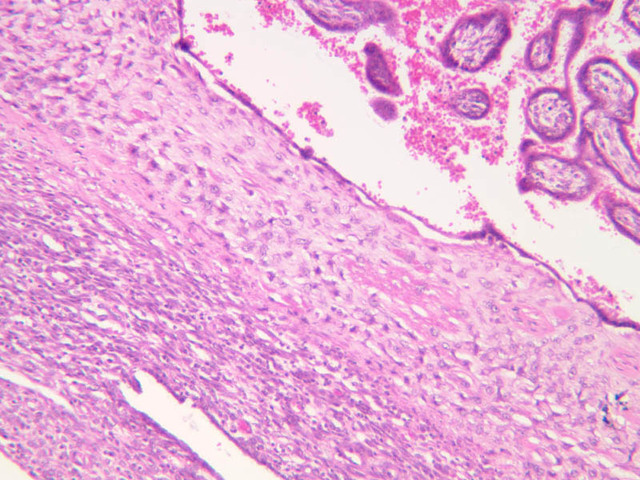

The wall of the uterine tube consists of three layers; a mucosa, a muscularis, and an adventitial/serous coat (B-96 [2.5x, 10x-labeled, 20x, 40x] [2.5x, 10x, 20x, 40x]; B-97, monkey uterus [2.5x, 10x, 20x, 40x]). The mucosa is organized into folds that vary in their degree of complexity with the tube regions. The mucosa is lined by a simple columnar epithelium consisting of two cell types, ciliated and non-ciliated, secretory (B-93 [10x, 20x, 40x-labeled]). The mucosal lamina propria consists of somewhat loose connective tissue and is highly vascular. No muscularis mucosae are present. The muscularis consists of two layers of smooth muscle, the inner being oriented in a circular fashion and the outer longitudinally.

The structure of the uterine tube is under the control of, and responds to, cyclic changes in the levels of steroid hormones. Structural alterations to provide favorable transport for the oocyte commence anew with the beginning of each cycle and peak at mid-cycle just before ovulation. These include increases in height and number of the ciliated cells as well as active secretion in the secretory cell. For the remainder of the cycle thereafter, dedifferentiation occurs. The cyclic changes occur to a greater extent in the upper ampulla and infundibulum. The margin of the infundibulum is drawn out into numerous finger-like processes called fimbrae. Microscopic examination of these will reveal that within the lamina propria are numerous large blood vessels, especially veins, as well as bundles of smooth muscle forming an intervening network. At the time of ovulation, the vessels become enlarged with blood, causing turgidity, which when combined with smooth muscle contraction brings the infundibular opening into close apposition with the ovarian surface.